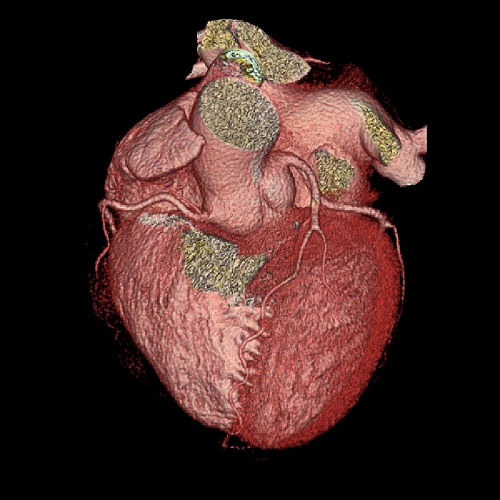

We utilize one of the few 64 slice CT scanners in North Texas that allows non-invasive diagnosis of such conditions as coronary artery disease (heart vessel blockage).  The heart vessels are displayed on our advanced 3D computer workstations where one of our doctors can make a diagnosis in minutes.  This procedure is much safer than cardiac catheterization.